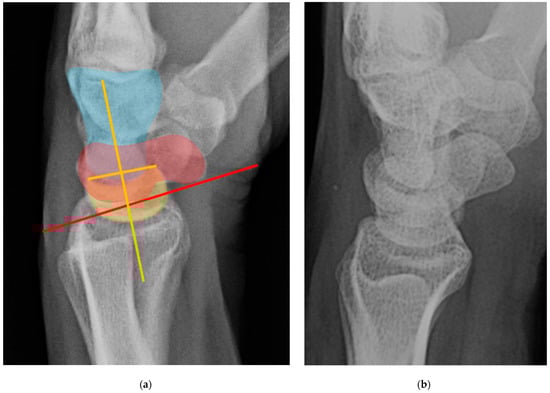

Similar to the role that disruption of the SLL plays in DISI, volar intercalated segment instability (VISI) deformity occurs when there is disruption of the lunotriquetral ligament (LTL) [23]. Because the anterior fibers of LTL are thickest, it is the main volar stabilizing element restricting the lunate from volar rotation relative to the capitate [4]. Rupture of LTL causes the capitolunate angle to increase beyond the normal range of less than 30°, in the opposite direction as seen with DISI. Because the scaphoid is usually still tethered to the lunate in VISI, it rotates in a volar direction with the lunate. On a lateral radiograph of a normal wrist, the capitolunate angle measures less than 30°, and if the angle measured greater than 30°, it would represent LTL rupture and VISI (Figure 33). VISI is considered a CID lesion when there is a traumatic etiology and CIND lesion if rheumatic. When this occurs with perilunate injury, it is classified as a CIC lesion as it involves ligaments and/or bone from proximal and distal rows. Management of VISI consists of early reduction and casting, closed reduction and fixation with K-wires, or capitolunate fusion.

Figure 33. (a) Lateral wrist radiograph with overlay showing excessive volar rotation of the lunate relative to the capitate, with an increased capitolunate angle beyond 30°. The white line is drawn through the capitate axis while a yellow line is drawn through the lunate axis. Capitate (blue), scaphoid (red), lunate (yellow). (b) Normal lateral wrist radiograph for comparison.